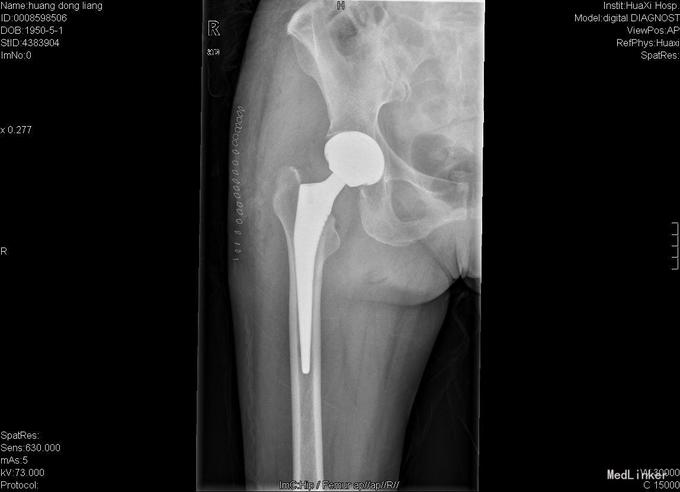

患者女,70岁,因"摔伤后右髋部疼痛、活动障碍10小时"入院,患者诉10小时前在家不慎滑倒,当即感觉右髋部疼痛、活动障碍,于当地医院急诊检查示:右股骨颈骨折,为求进一步诊疗故来我院。

查体:右髋部略水肿,右髋关节活动受限,不能负重。右髋部压痛(+),纵向叩击痛(+)。右髋关节活动受限,右膝及踝、足趾诸关节活动正常。 辅查:X线片示右股骨颈骨折,断端分离、错位。

入院诊断:右股骨颈骨折 诊疗计划:择期手术治疗,行右侧全髋关节置换。